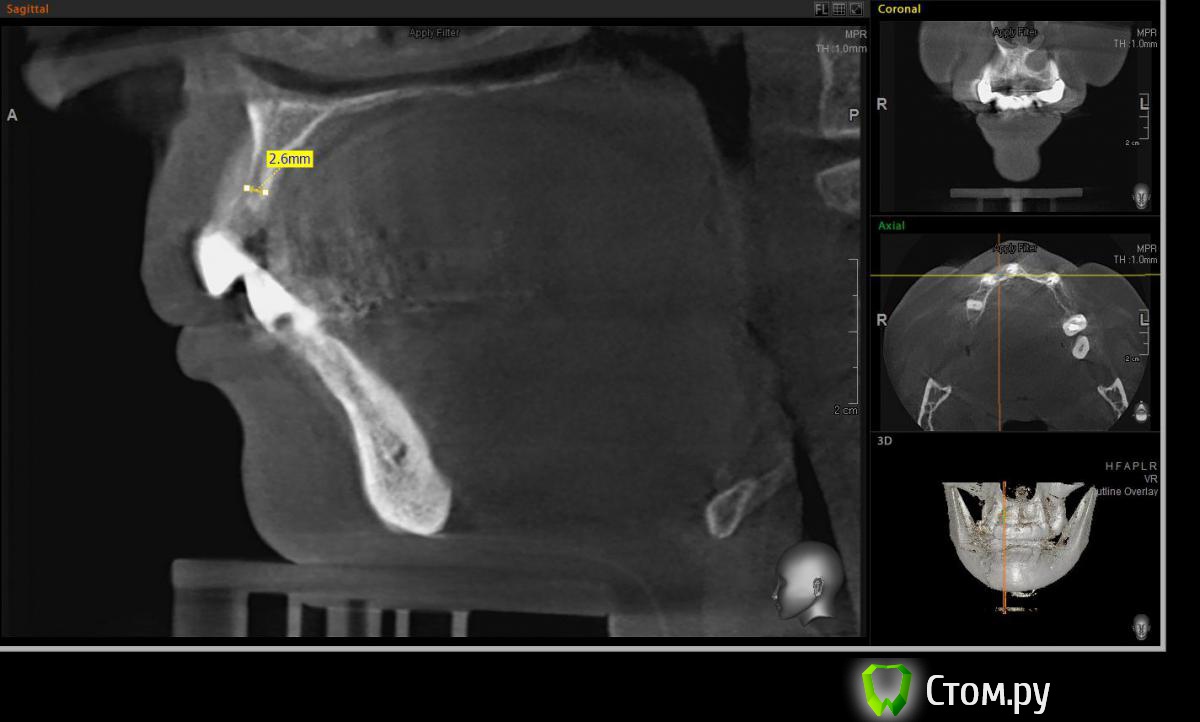

Евгений Ходыкин Опубликовано 22 июля, 2014 Автор Поделиться Опубликовано 22 июля, 2014 Дабы не плодить тем решил очередной случай выложить сюда Решили с пациенткой пока начать с в.ч. В планах имплантация в область отсутствующих 1.6, 1.4, 1.2, 2.1, 2.2, 2.4, 2.5. С 1.6 самому более менее все понятно, мануальных навыков хватит) Прошу помощи коллег относительно остальных областей. Фронт особливо печален... Забегая наперед скажу, что блоки еще не делал. Ауто точно пока брать не планирую, ибо нет даже теоретических навыков. Хочу начать все-таки с аллоблоков. У кого какие будут мнения, заранее спасибо) Ссылка на комментарий